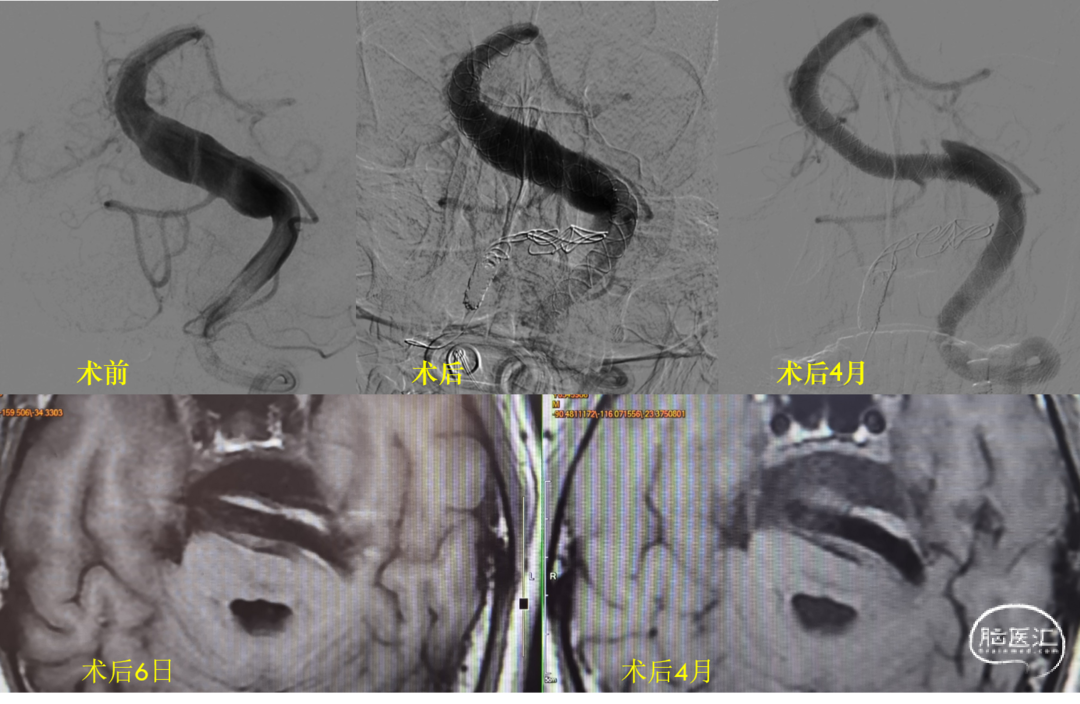

男性,44岁,头晕、复视,构音障碍1月余,mRS:1分,MR提示脑干梗死,基底动脉扩张。(图1)

图1

患者出院后自行康复,共济失调症状逐步改善,术后1月将替格瑞洛改为氯吡格雷75mg 1/日;术后4月复查时mRS:1-2分。造影提示管腔重塑良好,MR提示支架外血栓形成(图5)。予以停用氯吡格雷,等待二次复查。

图5